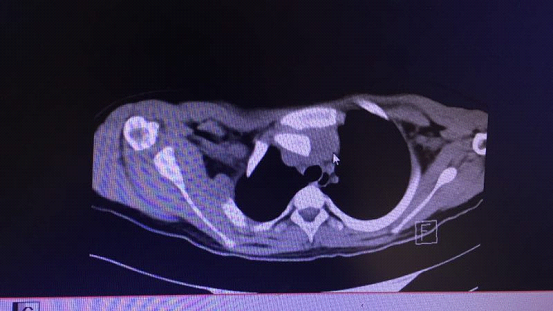

▲CT断层显示上纵膈压迫明显

由于小云锁骨胸骨端向后严重移位,压迫了胸腺、气管、头臂动脉、头臂静脉,且移位的锁骨胸骨端离头臂静脉仅2mm,距头臂动脉5mm,加上双肺多发渗出挫伤,病情十分危急。要挽救小云的生命,需紧急进行急诊手术。